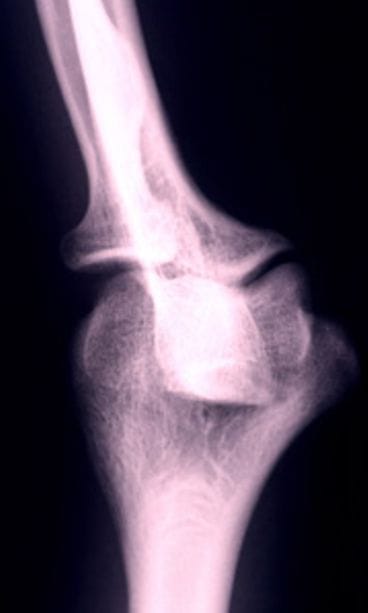

Vaihdevuotensa ohittaneet naiset kuuluvat osteoporoosin, eli luukadon, riskiryhmään automaattisesti. Tämä johtuu estrogeenihormonin tuotannon loppumisesta vaihdevuosien myötä. Kyseinen hormoni on yksi tärkeimmistä ja parhaimmista luun kestävyyttä parantavista tekijöistä.

Estrogeenin tuottamisen loputtua naisten luusto alkaa haurastua pikavauhtia, minkä takia hormonin merkitystä luun vankistamisessa ei pidä väheksyä: osteoporoosin iskiessä naiset voivat harkita myös estrogeenihoitoa luidensa vankistamiseksi.